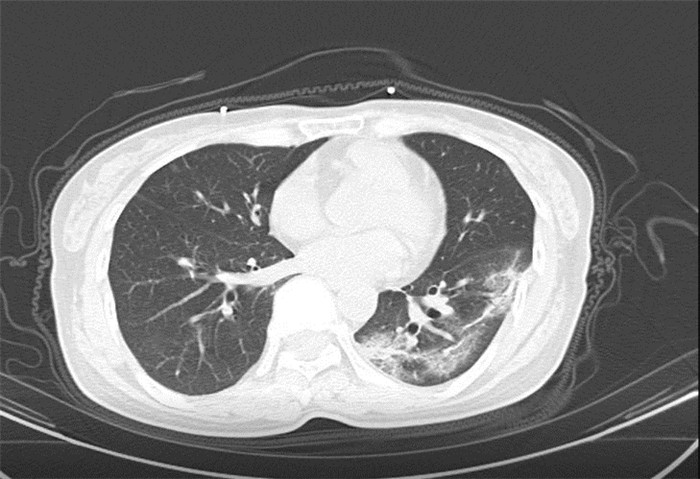

CT為當前首選篩查與診斷的主要影像學手段,胸部CT的病毒性肺炎檢出率高。

方舟CT(CT Ark)可以滿足全面的臨床功能,配置16層、32層、64層、128層CT,實現了低劑量掃描要求,配合NDI微劑量迭代技術,智能毫安調控技術,使各種場合下、各部位低劑量掃描得以實現;超高分辨率CT病灶靶掃描,使病灶的密度顯示更加精確,能夠顯示病灶內輕度的密度變化,有利于小病灶的密度定量分析和及時診斷。